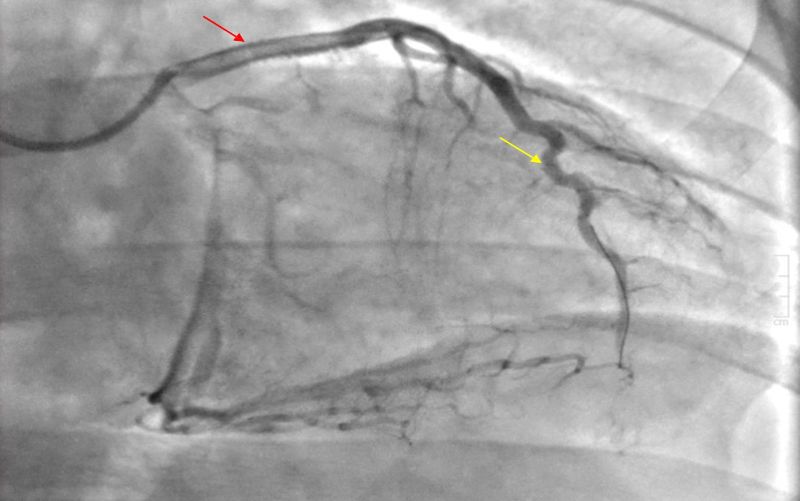

Figure 3: Electrocardiogram (EKG) shows ST elevations in leads I, aVL, V2-V4, and T-wave inversions in lead III, aVFThe patient was immediately taken to the cardiac catheterization lab, where a left heart catheterization revealed 90% thrombotic occlusion of the proximal and 100% occlusion of the distal Left Anterior Descending artery (LAD), as shown in Figure 4.

Figure 4: Angiograph indicated the presence of thrombi obstructing 90% of the proximal (red arrow) and 100% of the distal (yellow arrow) Left Anterior Descending artery (LAD).

Two drug-eluting stents – 4.0 X 20 Synergy XD and 4.0 X 8 Synergy XD – were placed in the proximal LAD lesion. There was TIMI 2 flow before, and TIMI 3 flow after the intervention was performed on the proximal LAD. Mechanical thrombectomy with a CAT6 RX kit and balloon angioplasty was performed on the distal LAD lesion. TIMI 0 flow improved to TIMI 2 flow after the procedure [Figure 5]. Blood flow to other coronary artery branches was normal. The patient was subsequently admitted to the Coronary Care Unit, where he underwent a significant hypercoagulability workup.